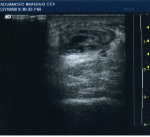

Achilles Tendon: Partial Thickness tear at the mid-malleolar level